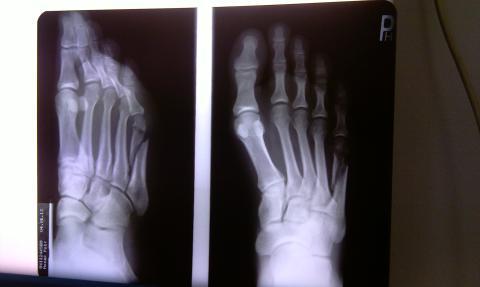

Dobrý deň,rad bych se zeptal i na nazor odjinud k prilozene fotografii rentgenu ze dne 4.6. Dne 29.4. jsem utrpel zlomeninu nartni kosti, nasledne jsem mel mesic sadrovou fixaci a od 28.5. po sundani teto fixace mam na teto noze ortezu. Dle konzultace s pani doktorkou z chirurgie je vse v poradku a za 14 dni bych mel zacit chodit jiz bez jakekoliv fixace, nicmene dle meho neni tato zlomenina vubec ve fazi srustani, jelikoz zlomene konce kosti na sebe nenavazuji. Po dotazu, zda by nebylo vhodne dratovani, me bylo sdeleno, ze ne. Je prosim normalni, ze po takrka 40 dnech muze zlomenina stale takto vypadat a zda je postup chirurgie spravny? Ptam se, jelikoz jsem doposud zadnou zlomeninu nemel a rad bych se vyvaroval pripadne dalsi zdlouhave lecbe v pripade ze by kost spatne srostla, ci event. trvaleho kulhani zpusobene spatnym srostenim. Velice dekuji za odpoved. Preji prijemny den Vsem!

Dobrý den,Snímek bych potřeboval vidět ve větším rozlišení, ale i z této fotky je patrné, že fraktura se nehojí zcela optimálně. Nejsem chirurg, takže se nemohou podrobněji vyjádřit. Doporučuji situaci konzultovat s dalším specialistou a zjistit jeho názor.